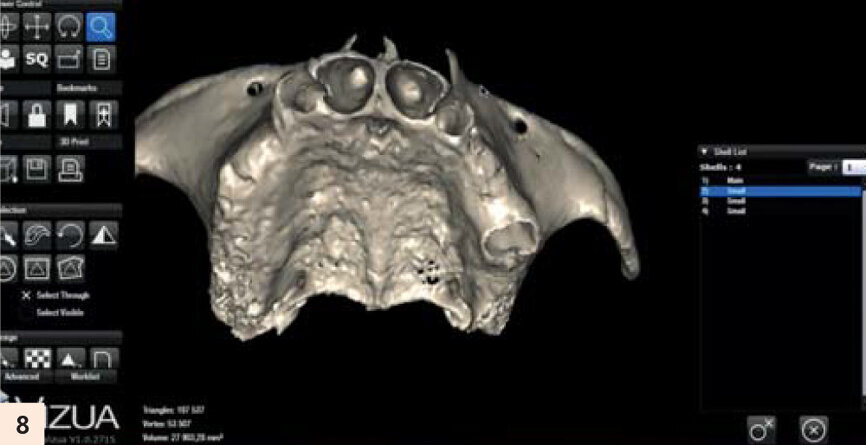

...et avec des extractions virtuelles.

L’important est de reproduire par l’empreinte en fin de chirurgie, l’occlusion enregistrée des semaines auparavant. La technique utilisée sera l’empreinte fractionnée, grâce à une gouttière callée sur des repères fixes que nous retrouvons en fin d’intervention (Fig. 5). Cette méthode a été décrite par Luc Gillot et Bernard Cannas qui font partie des pionniers de la MCI en France.9, 11 Ce cas clinique est complexe. Comme toute chirurgie, nous n’avons pas le droit à l’erreur. La planification sur ordinateur a permis de se familiariser avec les volumes osseux. Simuler la chirurgie permettrait d’éviter les pièges d’une anatomie complexe. En partenariat avec l’équipe Vizua et la Sapo implant, nousimprimons le maxillaire de notre patiente en individualisant les dents pour visualiser les alvéoles d’extraction (Figs. 6 et 7). Puis nous procédons au forage dans ce modèle imprimé en résine, en suivant notre planification. Nous appréhendons les difficultés de ce cas : la fine corticale du bloc incisif, la position exacte de l’implant en 15 dans la paroi antérieure du sinus droit... Quelle meilleure préparation que la simulation sur modèle ? (Fig. 8)